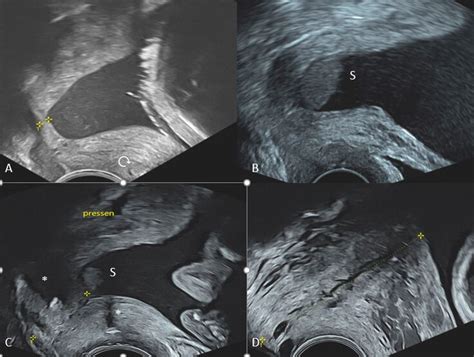

- Ultraschalluntersuchung: Die transvaginale Ultraschalluntersuchung ist die zuverlässigste Methode zur Bestimmung der Länge des Gebärmutterhalses (Zervixlänge) und zur Beurteilung des Muttermunds. Eine Verkürzung kann auf eine Zervixinsuffizienz hindeuten.

Die Messung der Zervixlänge ist entscheidend. Eine Zervixlänge von weniger als 25 mm wird als verkürzt betrachtet und birgt ein erhöhtes Frühgeburtsrisiko.